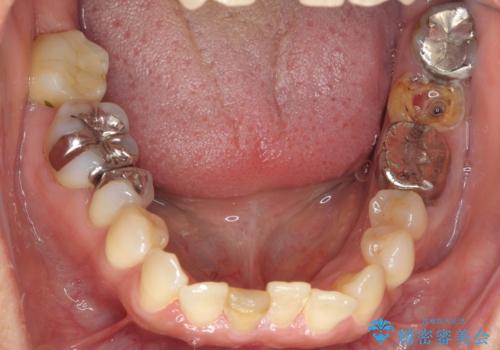

- 親知らずの移植をご希望し、遠方から来院された患者様です。

左下の奥歯(左下7)は破折しており保存不可能な状態でした。

ご希望により、隣の親知らず(左下8)を移植しました。

移植後、生着を待って根管治療及び補綴修復を行いました。